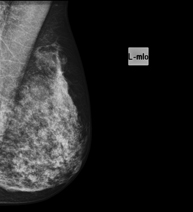

Mamografía digitalizada

La mamografía digitalizada es una técnica innovadora que permite estudiar la mama con una dosis baja de radiación, reduciéndola respecto al empleo de mamografía convencional. La imagen se digitaliza a partir de unos chasis especiales llamados CR. Gracias a estas técnicas de digitalización se obtienen excelentes imágenes, sobre todo en mamas de difícil estudio como las glandulares que se presentan en la mamografía como una mama densa, detectando en este grupo de pacientes mejor las tumoraciones.